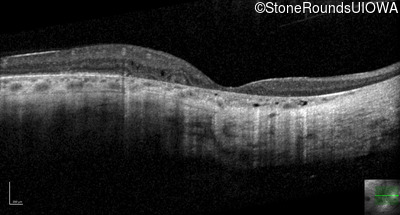

Optical Coherence Tomography - Left - 20/32 -2 sc

Exemplar / OCT Stack